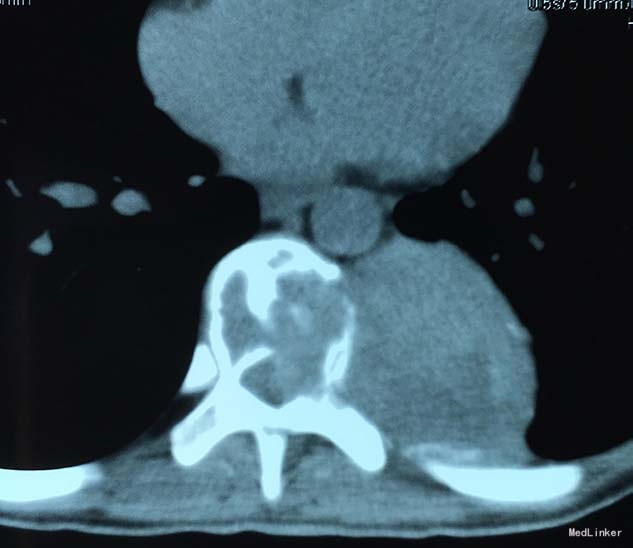

查体:脊柱外观无明显畸形,颈椎活动度正常,胸背部可见纵向长约15cm切口,皮肤钉缝合,伤口愈合可,无红肿渗液。胸椎9-10体左侧棘突旁局部压痛(+)、叩击痛(-),压头试验阴性,双侧侧臂丛牵拉实验(-),双上肢肌张力、运动、感觉及反射无明显异常、躯体感觉无明显减退,双下肢髂腰肌、股四头肌、胫前肌肌力IV级,感觉正常,双下肢直腿抬高试验(-),双侧腱反射对称略活跃,双侧Hoffman征(-),双侧Babinski征(-),双侧髌阵挛(-),踝阵挛(-)。 辅助检查:2015-11外院胸椎MRI检查发现T9-10节段椎体肿瘤并椎旁软组织肿块形成,肿块突入胸腔占位

诊断:胸椎椎体肿瘤(T9-10) 治疗:先于外院行1期后路椎弓根钉固定融合手术,然后转入我院行介入下术前椎体节段血管栓塞手术,第二天行经左侧胸腔入路椎体肿瘤病灶刮除并钛网植骨植入重建手术。术后恢复满意。复查MRI显示肿瘤病灶基本完全切除。